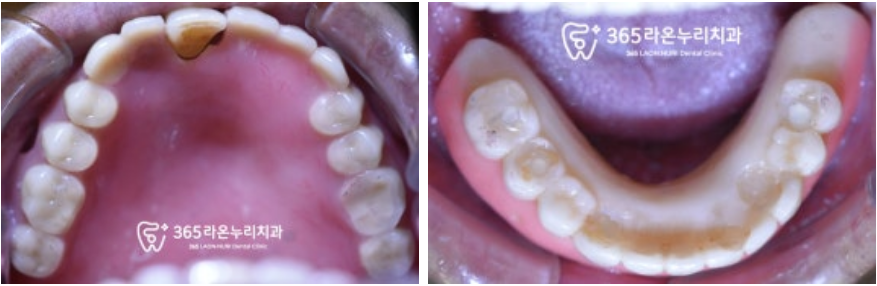

■ 1. 초진

위와 같은 이유로 찾아오신 환자였습니다.

구강을 살펴보면

남아있는 이가 몇 개 없고

그마저도 이미 많이 흔들리고 있었습니다.

장기간 이가 없이 지내시다 보니

턱도 그에 맞추어 조금씩

변화가 일어나고 있었으며

무엇보다 식사를 하기 힘드니

환자께서는 전신 건강도

안 좋아지고 있다며 빠른 해결을 원하셨습니다.